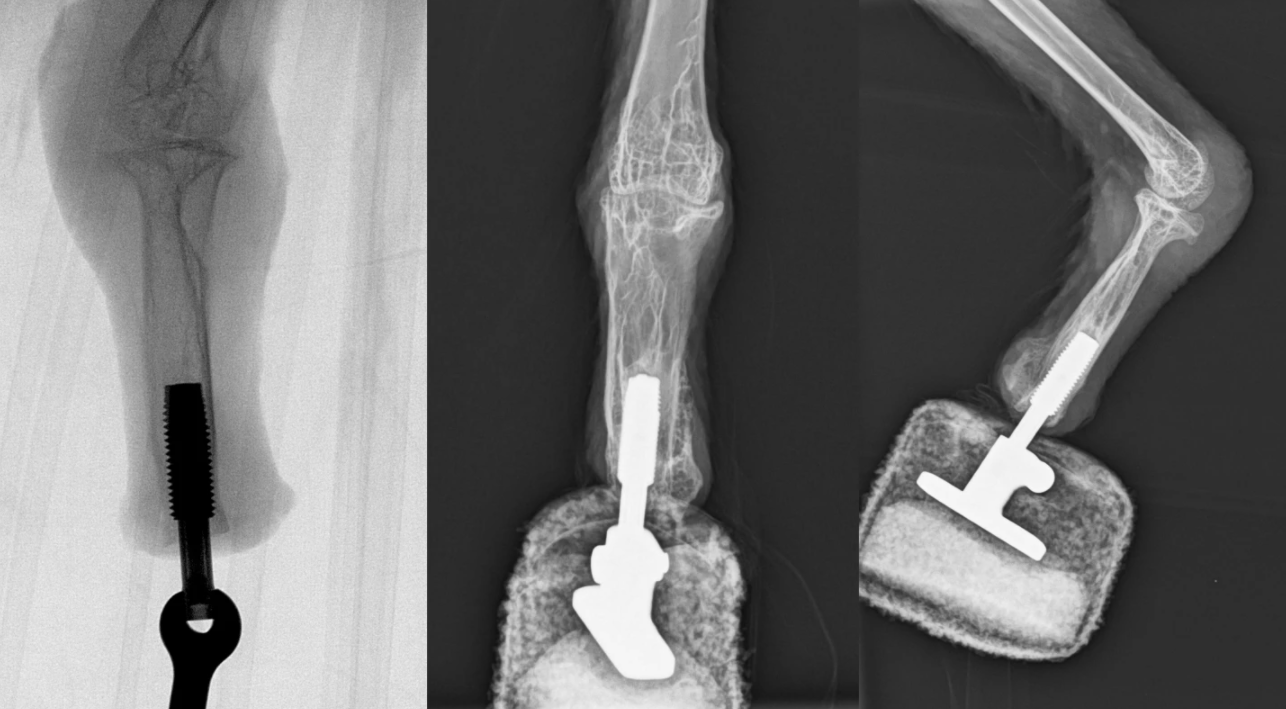

据外媒New Atlas报道,尽管已经有鸟类接受了绑带式假肢,但科学家们现在报告说,他们首次成功地将“假肢”直接整合到一只胡兀鹫的残余腿骨上。他们将这种动物描述为世界上第一只“仿生鸟”。

这只鸟被命名为“米娅”,是一只雌性胡兀鹫,是欧洲最大的一种飞鸟。它被安置在位于奥地利哈林塞的猫头鹰和猛禽保护区。“米娅”最初被带入保护区时,脚部严重受伤,最终不得不被截肢。

虽然较小的鸟类可能只用一只脚就能搞定,但这样的损失会使较重的鸟类(如胡兀鹫)很难着陆、行走或按住它们的猎物。考虑到这些问题,维也纳医科大学的一个小组决定给“米娅”植入一个永久连接的新“假肢”。